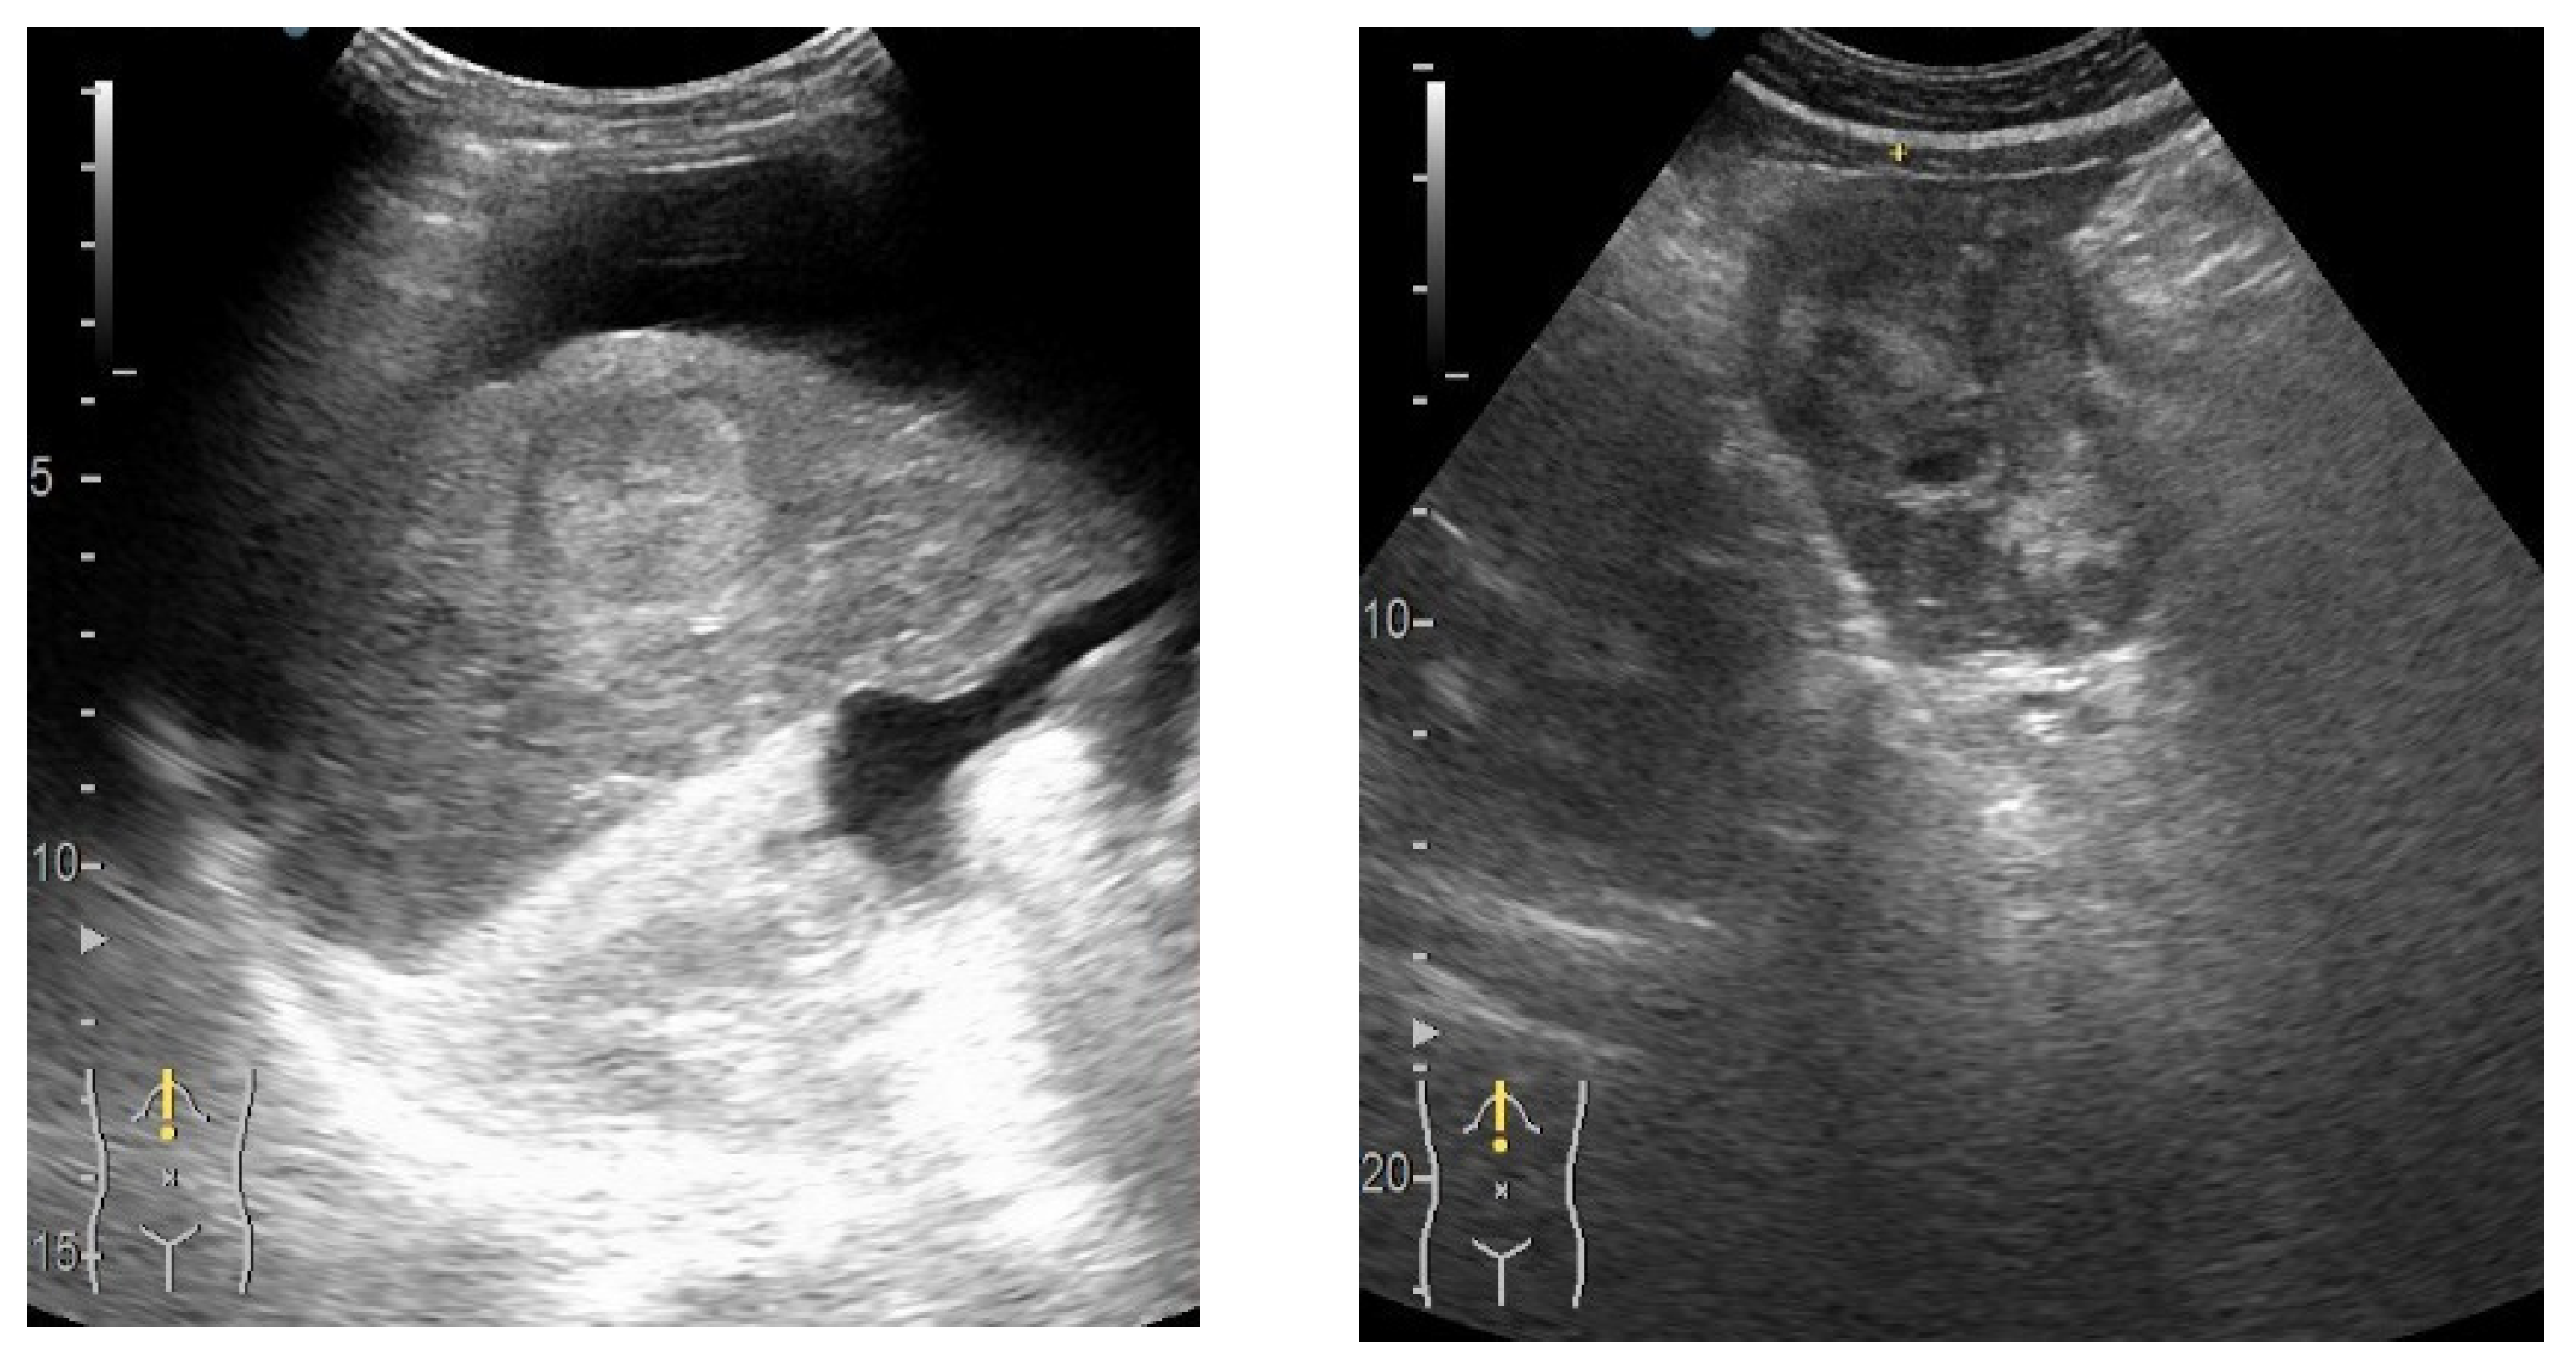

2.1. Data Acquisition

2.2. Data Preprocessing